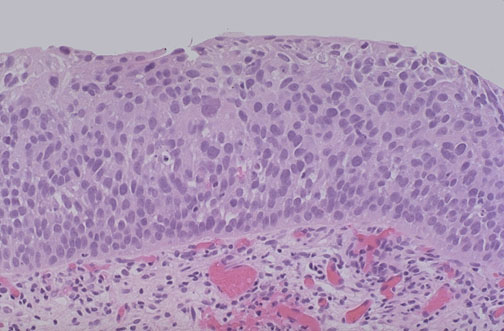

| The causative factors for urothelial carcinoma typically act upon the entire extent of the transitional epithelium in the urinary tract, and it is common for areas of neoplasia to arise multifocally. Seen here is urothelial carcinoma in situ. The abnormal cells are confined to the epithelium above the basement membrane. This area was present in a random bladder biopsy in a patient who also had a grossly visible lesion on cystoscopy. |